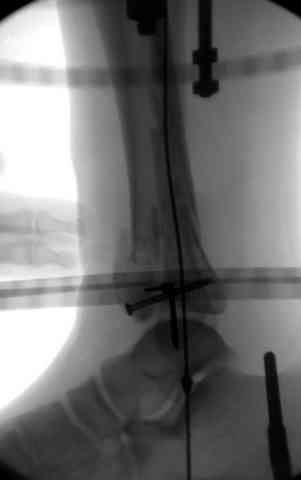

При лечении внутрисуставных переломов типа "Pilon"

или "Tibial Plateau" на голени, применение простых

наружных фиксаторов типа "Spanning ExFix" или "Travelling ExFix" стал одним из стандартом этапного лечения.

В первые часы после поступления больным экстренно накладывается простой фиксатор из двух поперечно проведенных стержней или сооружается "Delta

Frame" в зависимости от места локализации, и проводится дистракция.

Здесь выставлена пара случаев перелома пилона, оба

случая леченные этапным наружным фиксатором.